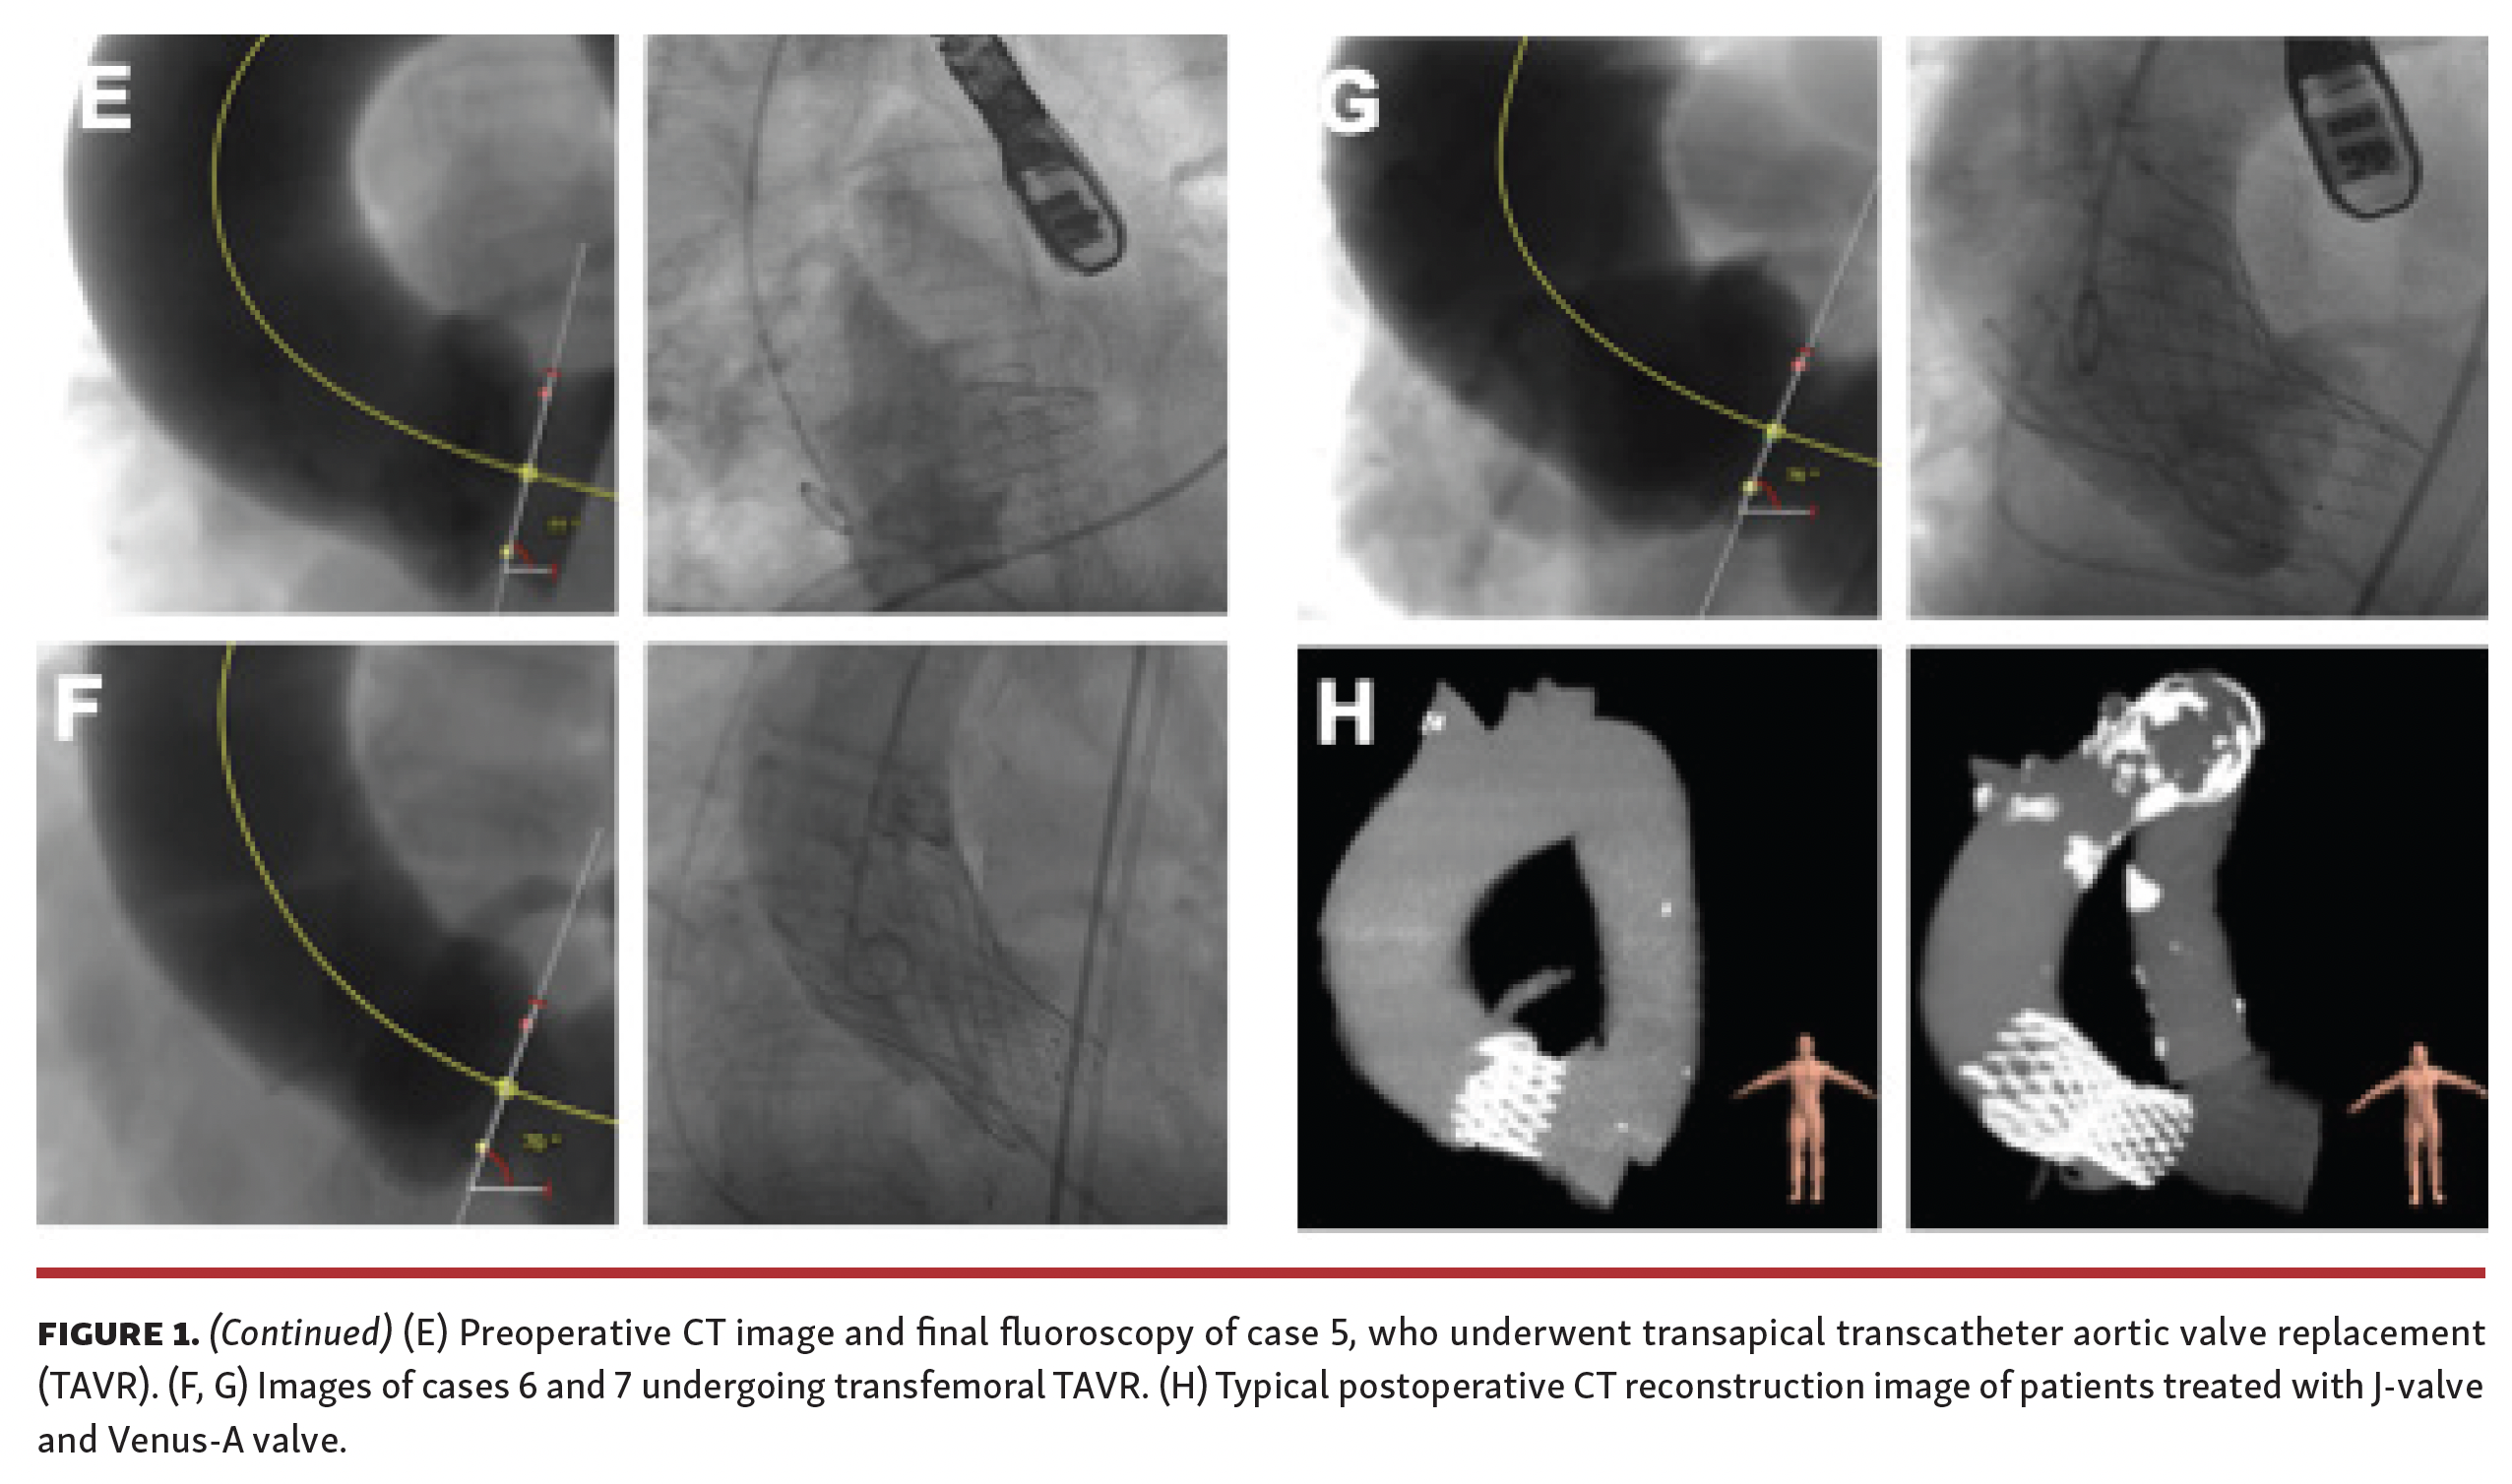

Transcatheter aortic valve replacement (TAVR) is not the preferred therapy for pure aortic regurgitation (AR). Extremely horizontal aorta (aorta root angle ≥70°) is regarded as an “off-label” use in self-expanding TAVR. This case series enrolled 7 consecutive pure AR patients who had extremely horizontal aorta and underwent self-expanding TAVR from the TORCH registry (NCT02803294). The mean age was 74.1 ± 8.3 years and the Society of Thoracic Surgeons (STS) score was 3.8 ± 1.5%. All patients lacked calcification at the aortic root. Transapical TAVR with a J-valve (Jiecheng) was performed in 5 patients and transfemoral TAVR with a Venus-A valve (Medtech) was performed in 2 patients (Figure 1 Part 1 and Figure 1 Part 2).

Case 1 received permanent pacemaker implantation and suffered a non-disabling stroke, while case 4 and case 5 suffered major bleeding during 30-day follow-up. Detailed aortic angulation measurement and fluoroscopy during the procedure are shown in Figure 1 Part 1 and Figure 1 Part 2. Nevertheless, procedural success was achieved in all patients according to Valve Academic Research Consortium-2 definitions and no patients were at New York Heart Association class III/IV at 30 days. To the best of our knowledge, this is the first study to report successful self-expanding TAVR for pure AR with extremely horizontal aorta, revealing the feasibility of both transapical and transfemoral TAVR in this challenging population.